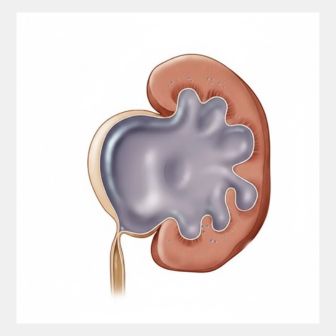

RECONSTRUCTIVE UROSUREGRIES

Professional medical services